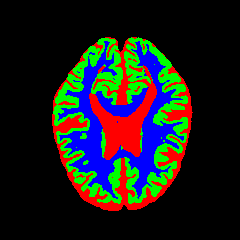

• OASIS-1 [34]: Derived from the Open Access Series of Imaging Studies, this dataset comprises T1-weighted MRI scans from 421 subjects (aged 18–96). The images were acquired with a resolution of 176×208176\times 208 pixels and a slice thickness of 1.25 mm (TR=9.79.7 ms, TE=4.04.0 ms, TI=2020 ms). Following standard protocols, we utilize the provided manual segmentation masks for Cerebrospinal Fluid (CSF), Grey Matter (GM), and White Matter (WM).

• MRBrainS13 [35]: From the MICCAI 2013 challenge, this dataset contains multi-sequence scans of 20 subjects acquired on a 3.0T Philips Achieva scanner. It provides T1 (TR: 7.97.9 ms, TE: 4.54.5 ms), T1-IR, and T2-FLAIR sequences. All scans are co-registered and bias-corrected with a voxel spacing of 0.96×0.96×3.000.96\times 0.96\times 3.00 mm. We utilize the provided labels for CSF, GM, and WM segmentation.

7 Qualitative Evaluation

Fig. 8 and Fig. 10 provide qualitative comparisons on the OASIS-1 and MRBrainS13 datasets, respectively. It is visually evident that the baseline predictions (c) and standard augmentations (e.g., (d), (g), (i)) frequently suffer from noisy artifacts, blurred boundaries, and mis-segmentation of intricate anatomical structures. In stark contrast, our ”Ours+” enhanced methods (e.g., (e), (h), (k)) consistently produce segmentation maps that are visibly cleaner, more spatially coherent, and demonstrate significantly sharper adherence to the Ground Truth (b). This superior fidelity is particularly noticeable in the complex sulcal patterns and holds true across all three backbones (rows), confirming that our framework yields more robust and anatomically plausible results.